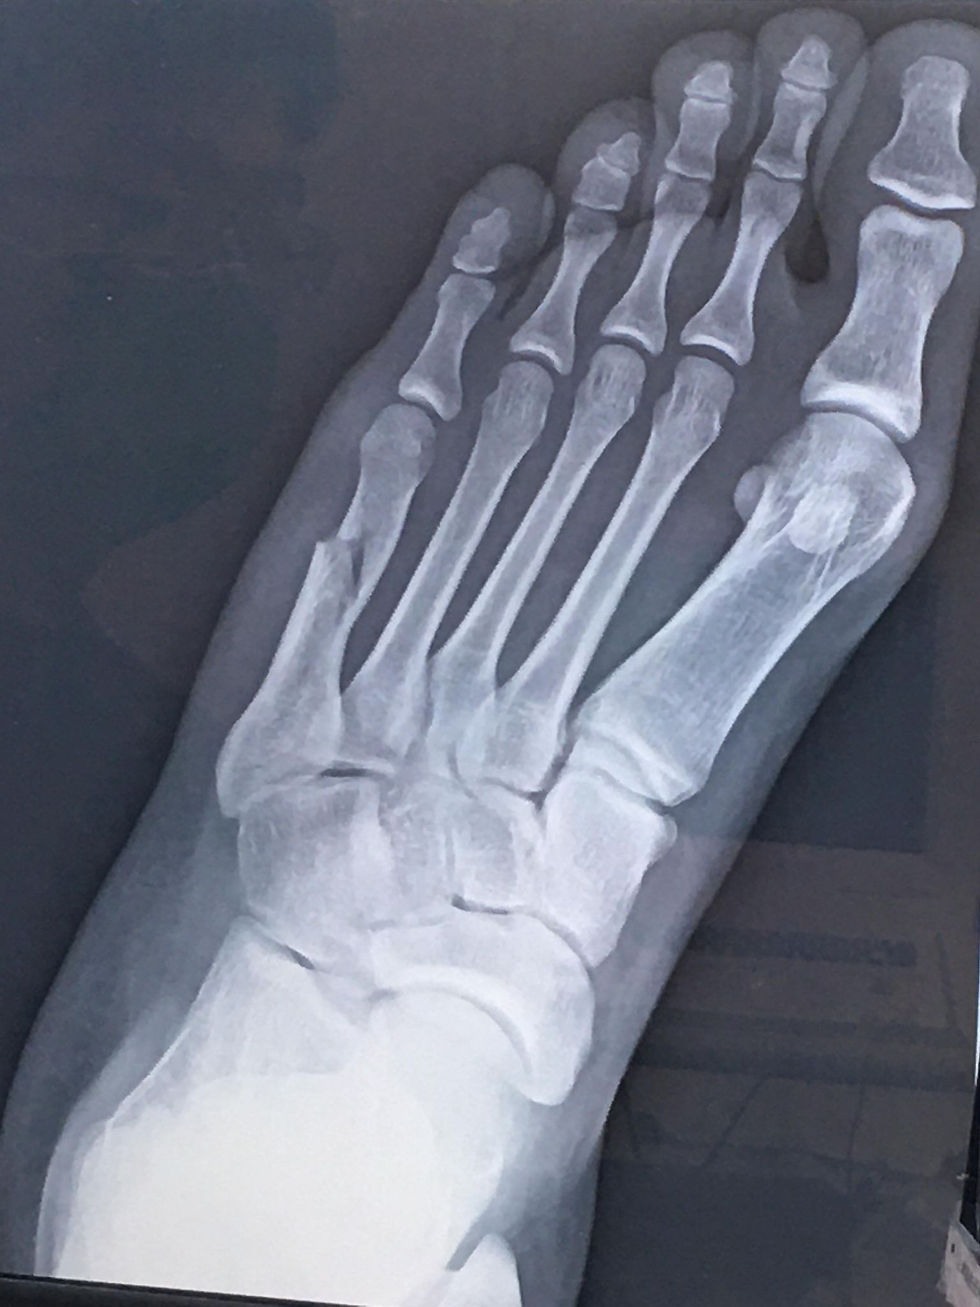

你所不知道的賽後精彩狀況|冠軍跳到自己腳掌骨折

當小編中秋連續假日聯絡冠軍得主,唐誼很震驚自己也可以獲得冠軍排名,

關心活動最後一天激烈的完賽之後,是否已經有好好休息恢復體力,但唐誼在電話裡卻笑笑地說,當天結束感覺腳軟自己在家從客廳走到廚房,不小心單腳翻船造成骨折,聽到喀嚓一聲,哇…當下聽到立刻被震驚到,收到唐誼發來的照片真的很為她擔心。

但善解人意的美眉馬上以很樂觀的語氣安慰起主辦方,還送小編一張腳比愛心的照片。這樣可愛又善良的小朋友,特別令人喜歡,不論有繩還是無繩,唐誼堅持到活動最後一分鐘的精神,可以證明不會輕言放棄自己的努力,希望她盡快早日康復,重回蹦蹦跳跳的每一天。主辦方真心感謝,每一位認真投入參加比賽的選手,你們展現努力不懈的運動家精神,在這紛擾的疫情年代,激勵了許多虛擬世界愛運動的朋友。